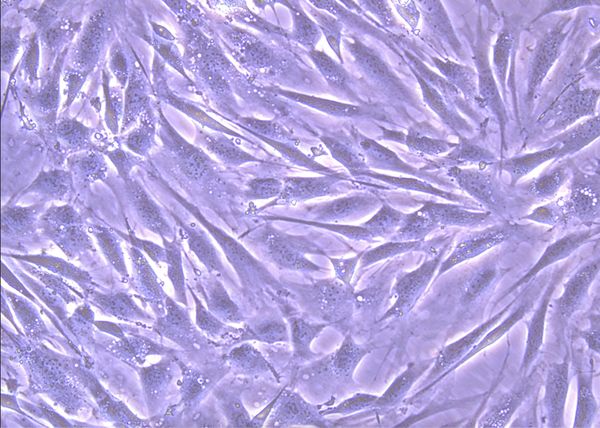

Stem Cells Beneath the Microscope